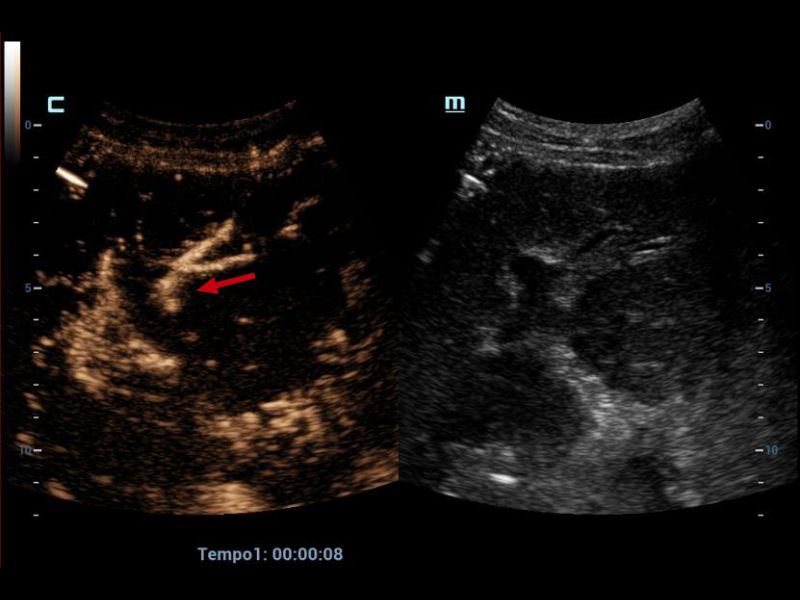

Left hepatic artery with adequate opacification (red arrow).

Figure 5. Left hepatic artery with adequate opacification (red arrow).